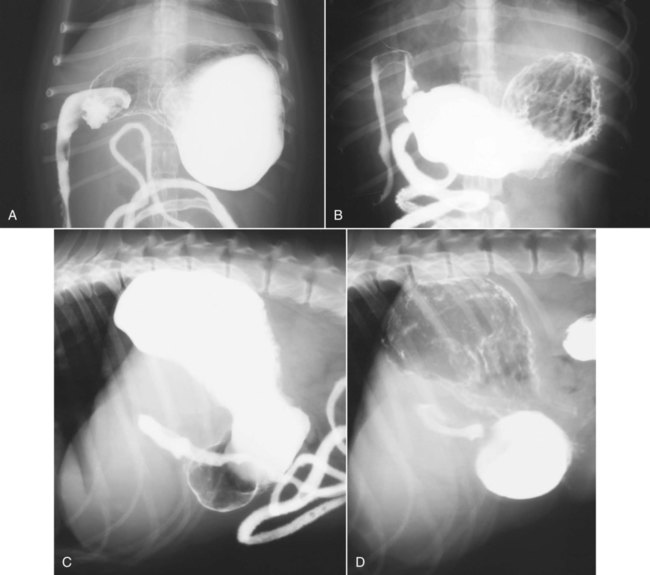

Thick tortuous folds or lobulated filling defects in the cardia or fundus. Right gastroepiploic artery inferiorly and left gastroepiploic artery and short gastric arteries superiorly fundus of the stomach. Results of surgical treatment of carcinoma of the esophagus and gastric cardia. The collection of cases presented here comprises only that material which is rare in our experience or quite new to us.

A healthier weight from surgery can help improve or resolve many obesity related conditions such as type 2 diabetes high blood pressure joint pain heart disease and more. Medically treated small gastric ulcer. Left and right gastric veins drain to portal vein. Ugis has a 70 90 detection rate.